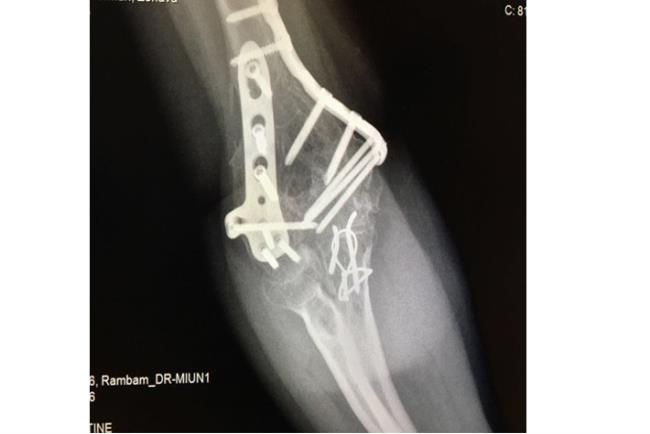

בשלב הראשון יתבצע צילום רנטגן. אם עולה חשד לכך שהשבר מערב גם את המפרק תתבצע גם בדיקת CT לשם הדמיה תלת ממדית של האזור הפגוע וחלקי השבר אותם יש להרכיב כדי להשיב למפרק את תנועתו התקינה. לרוב, כדי לטפל בשברים מורכבים יתבצע ניתוח ולא קיבוע בגבס.מטרת הטיפול בגבס היא קיבוע המצב הקיים ועל כן במקרה של שבר מורכב טיפול זה לא יועיל בהשבת התפקוד המפרקי. לכן, כדי להשיב את המצב לקדמותו יש צורך בפתיחת המפרק, העמדת כל אחד מחלקי העצם במקומו וחיבור החלקים אחד אל השני. הניתוח והקיבוע נעשים ע"י פלטות ברגים ומסמרים תוך לשדיים העשויים טיטניום או סוג של פלדת אל חלד.

קיבוע של שבר במרפק והחלפת ראש רדיוס | באדיבות פרופ' דורון נורמן